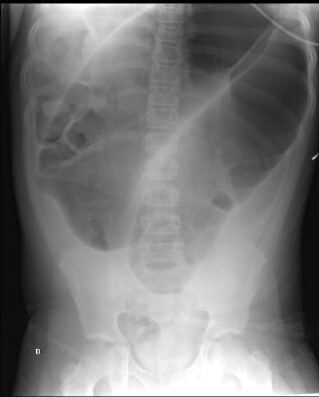

AXR - usually DIAGNOSTIC - sigmoid looks like COFFEE BEAN in LIF; if the ileocaecal valve is incompetent, the AXR will also show signs of small bowel dilatation. In caecal there will be small bowel dilatation.

What does the 3,6,9 rule refer to in AXR?

Small bowel = 3cm diameter

Caecum = 9cm

Colon = 6cm

NB: valvulae conniventes = small bowel

haustral lines = large bowel